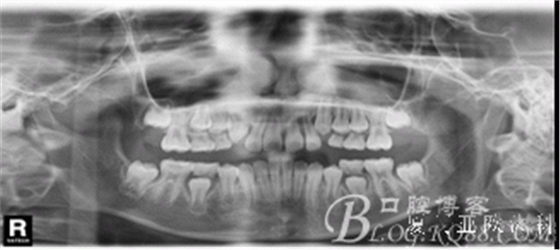

全頜曲面斷層片:尚未萌出的恒牙牙胚均存在。

診 斷:安氏I類錯(cuò)合(III類傾向)。骨骼III類關(guān)系。凹面型:上頜劣生長(zhǎng)、下頜過生長(zhǎng)。上頜尖牙萌出間隙不足。前牙骨性反咬合。